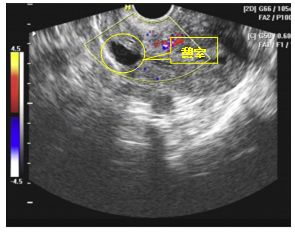

很简单,去医院做个经阴道三维彩超,记住,是三维!三维彩超可以从矢状位及冠状位去观察憩室,而二维做不到。你会说,磁共振(MR)也可以啊!但是磁共振贵啊,经阴道三维彩超不仅价廉,而且无创。